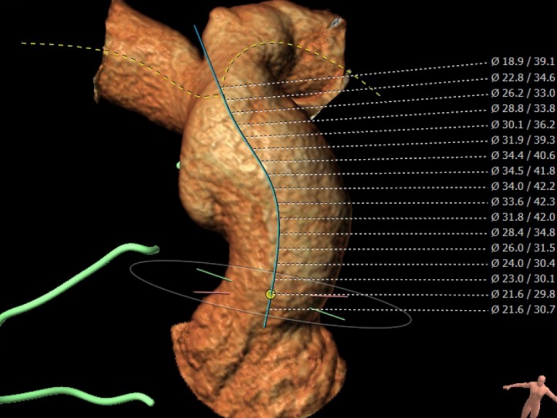

CT重建肺动脉

主肺动脉腰部截面